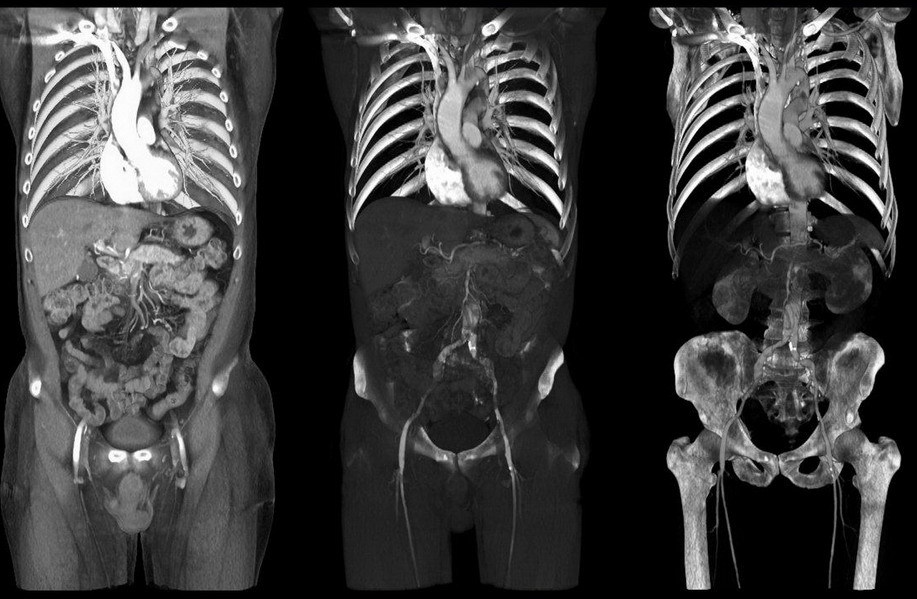

Theo nội dung vụ việc, bà Tú đến BV Đa khoa TP. Cần Thơ khám bệnh. Kết quả chụp CT cho thấy thận phải tốt, thận trái ứ nước độ III – IV, có sạn buộc phải mổ. Ngày 6/12/2011, bà Tú được bác sĩ chỉ định mổ nội soi thận trái ứ nước.

Theo biên bản họp hội đồng chuyên môn, các chuyên gia xác định: Trên phim CT - Scan, có thể dễ dàng thấy hình ảnh thận móng ngựa. Nhưng do bác sĩ chẩn đoán hình ảnh và phẫu thuật viên đều không nhận định được thận hình móng ngựa trước và trong lúc mổ nên dẫn đến sai lầm khi phẫu thuật. Đây là lỗi nhận định của kỹ thuật viên.